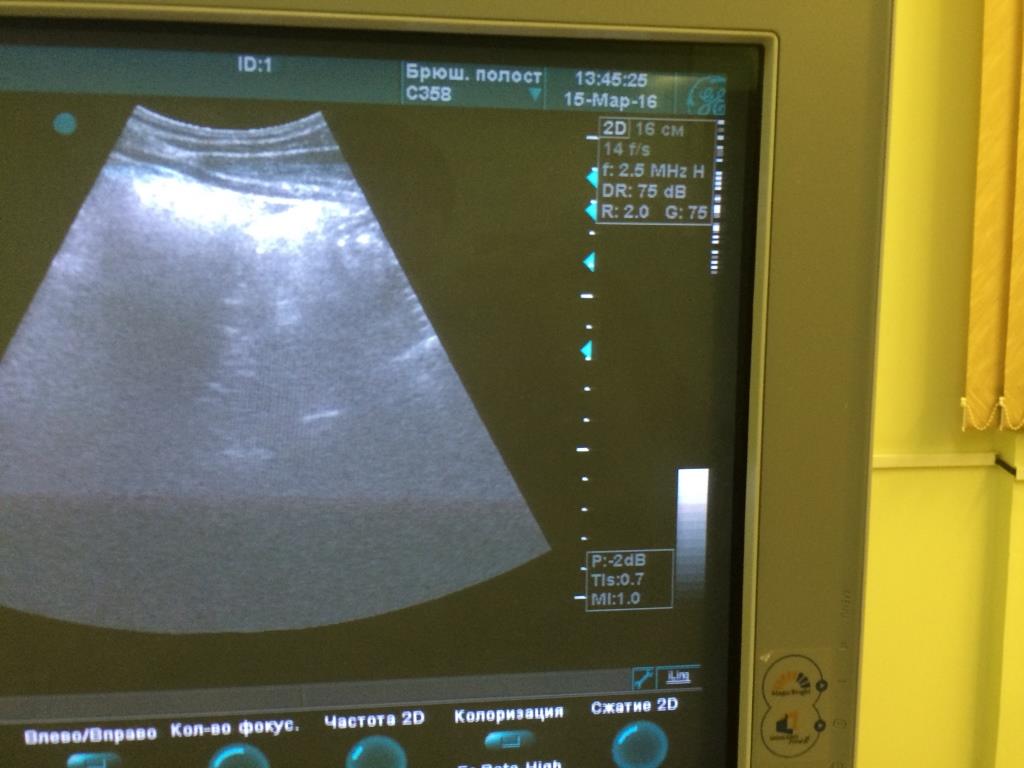

Аппарат Vivid 3 Pro корпорации General Electric Company (производственно-торговый бренд - "GE"), США, 2007 года.

При работе на конвексном и линейном датчике появляется картинка как на фото. Если убираю фокусные зоны либо понижаю частоту дефект пропадает.

Датчики вставлены в разные разъёмы. На конвексном есть небольшой порез акустической линзы, линейный без повреждений.

Предполагаю, что дело не в датчиках.